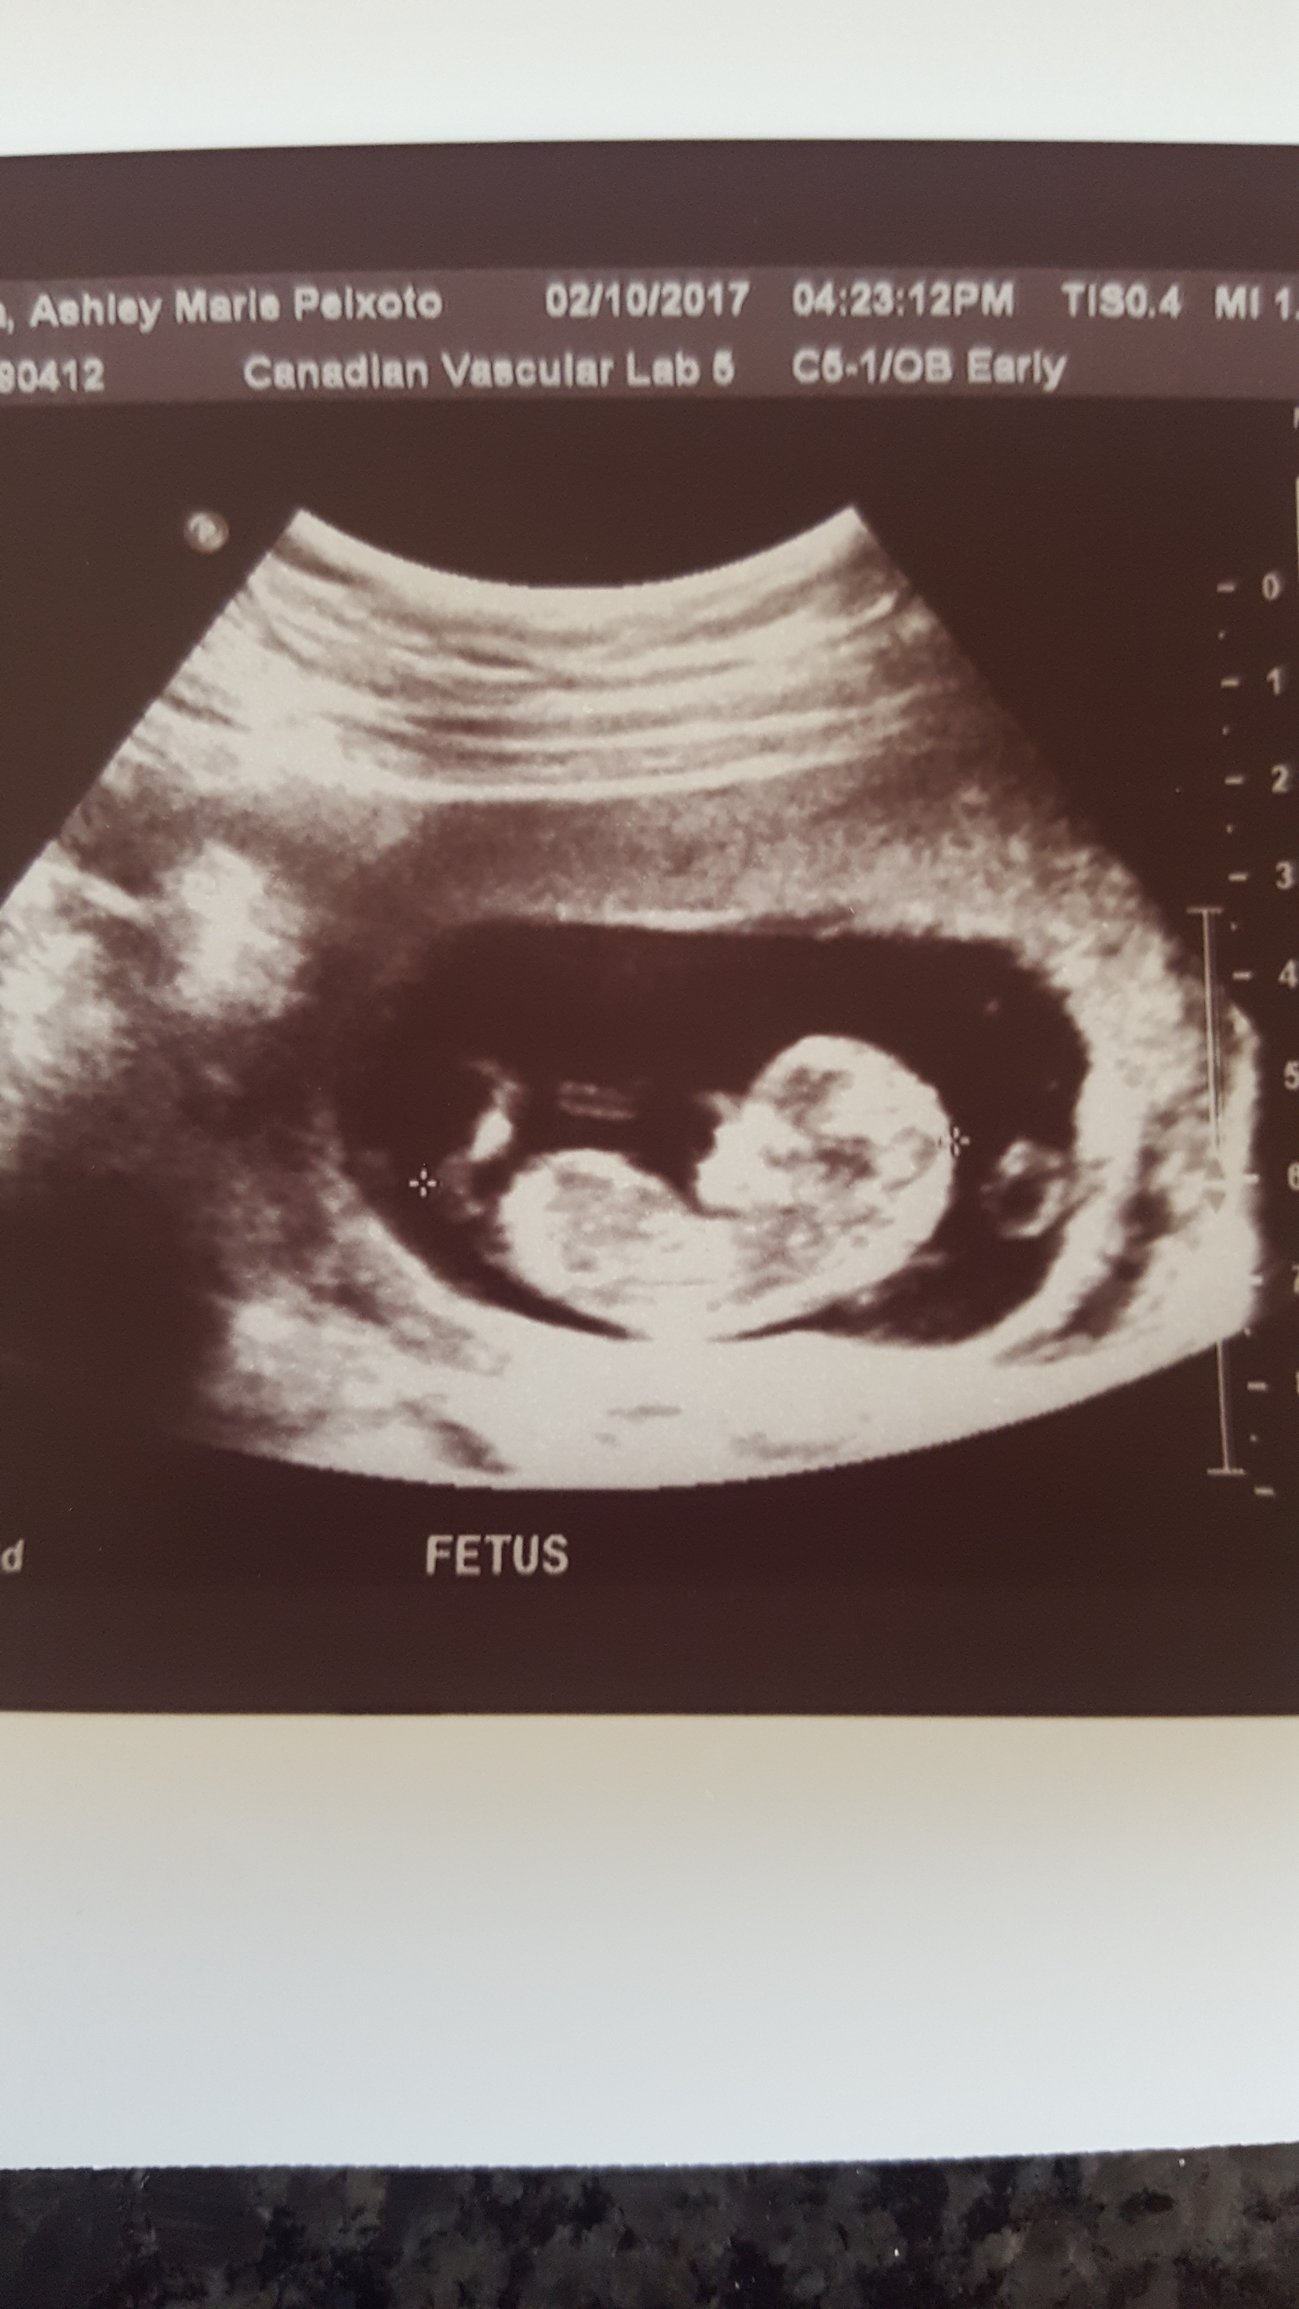

@lindsye...as I said above ... my ultrasound was today. October 2 2017 ...2/10/2017. 12 weeks today. A few people have posted about this skull theory so I was just throwing it out there to see...

Ohhh we all read it as February 2 but it's October 2 just the month is in the middle. Fyi "theories" on the sex of the baby don't go over well here I'd search for the other posts like this to see the responses. You'll have to wait for the ultrasound at 18-20 weeks unless you can get the early blood screening. Good luck!

@ingogliababy did you read the other skill theory posts? It didn't go over well. As far as the date, Americans put the month first. I am assuming Canadians put the day first. Just a cultural differences.

Ah ok, apologies @ingogliababy - the typical dating convention in the US is MM/DD/YEAR so that was the source of my confusion.

I would still point out that you might want to remove the personally identifiable information from your photo, but have nothing to add about the possible sex of your baby. Congrats!